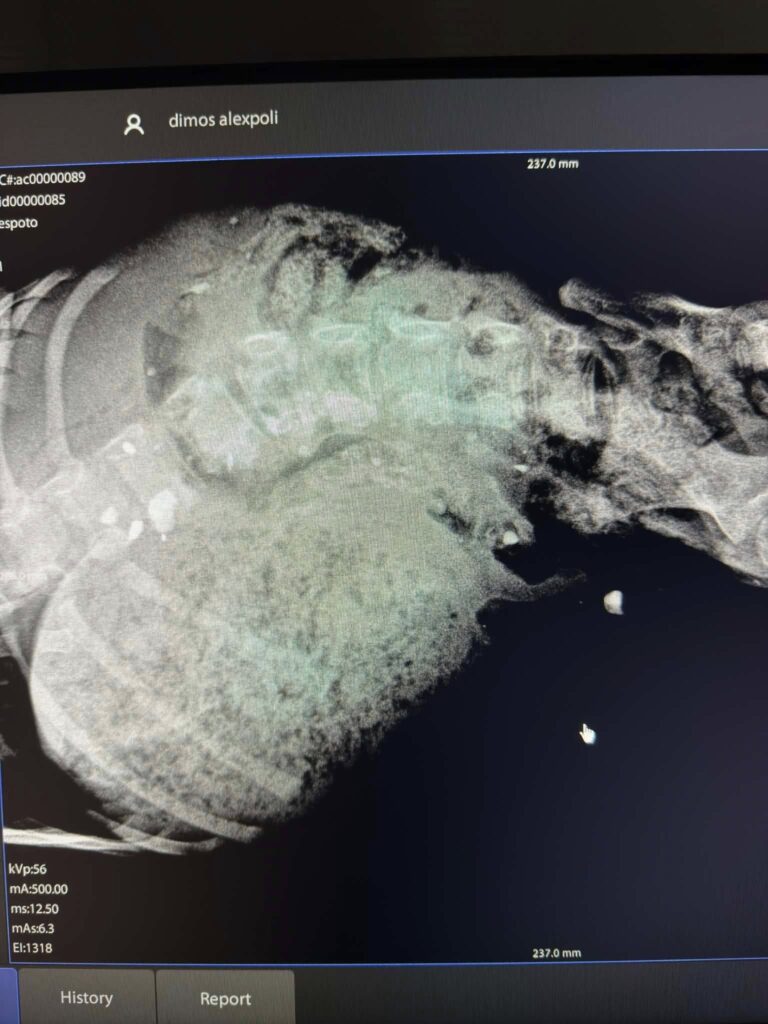

Η ακτινογραφία της φρίκης – Κουτάβι γεμάτο σκάγια

Το κουτάβι μεταφέρθηκε σε ημιλιπόθυμη κατάσταση, με τους γιατρούς να διαπιστώνουν διασπορά από σκάγια σε όλο του το σώμα. Η ακτινογραφία «μίλησε» και πάγωσε τους πάντες.